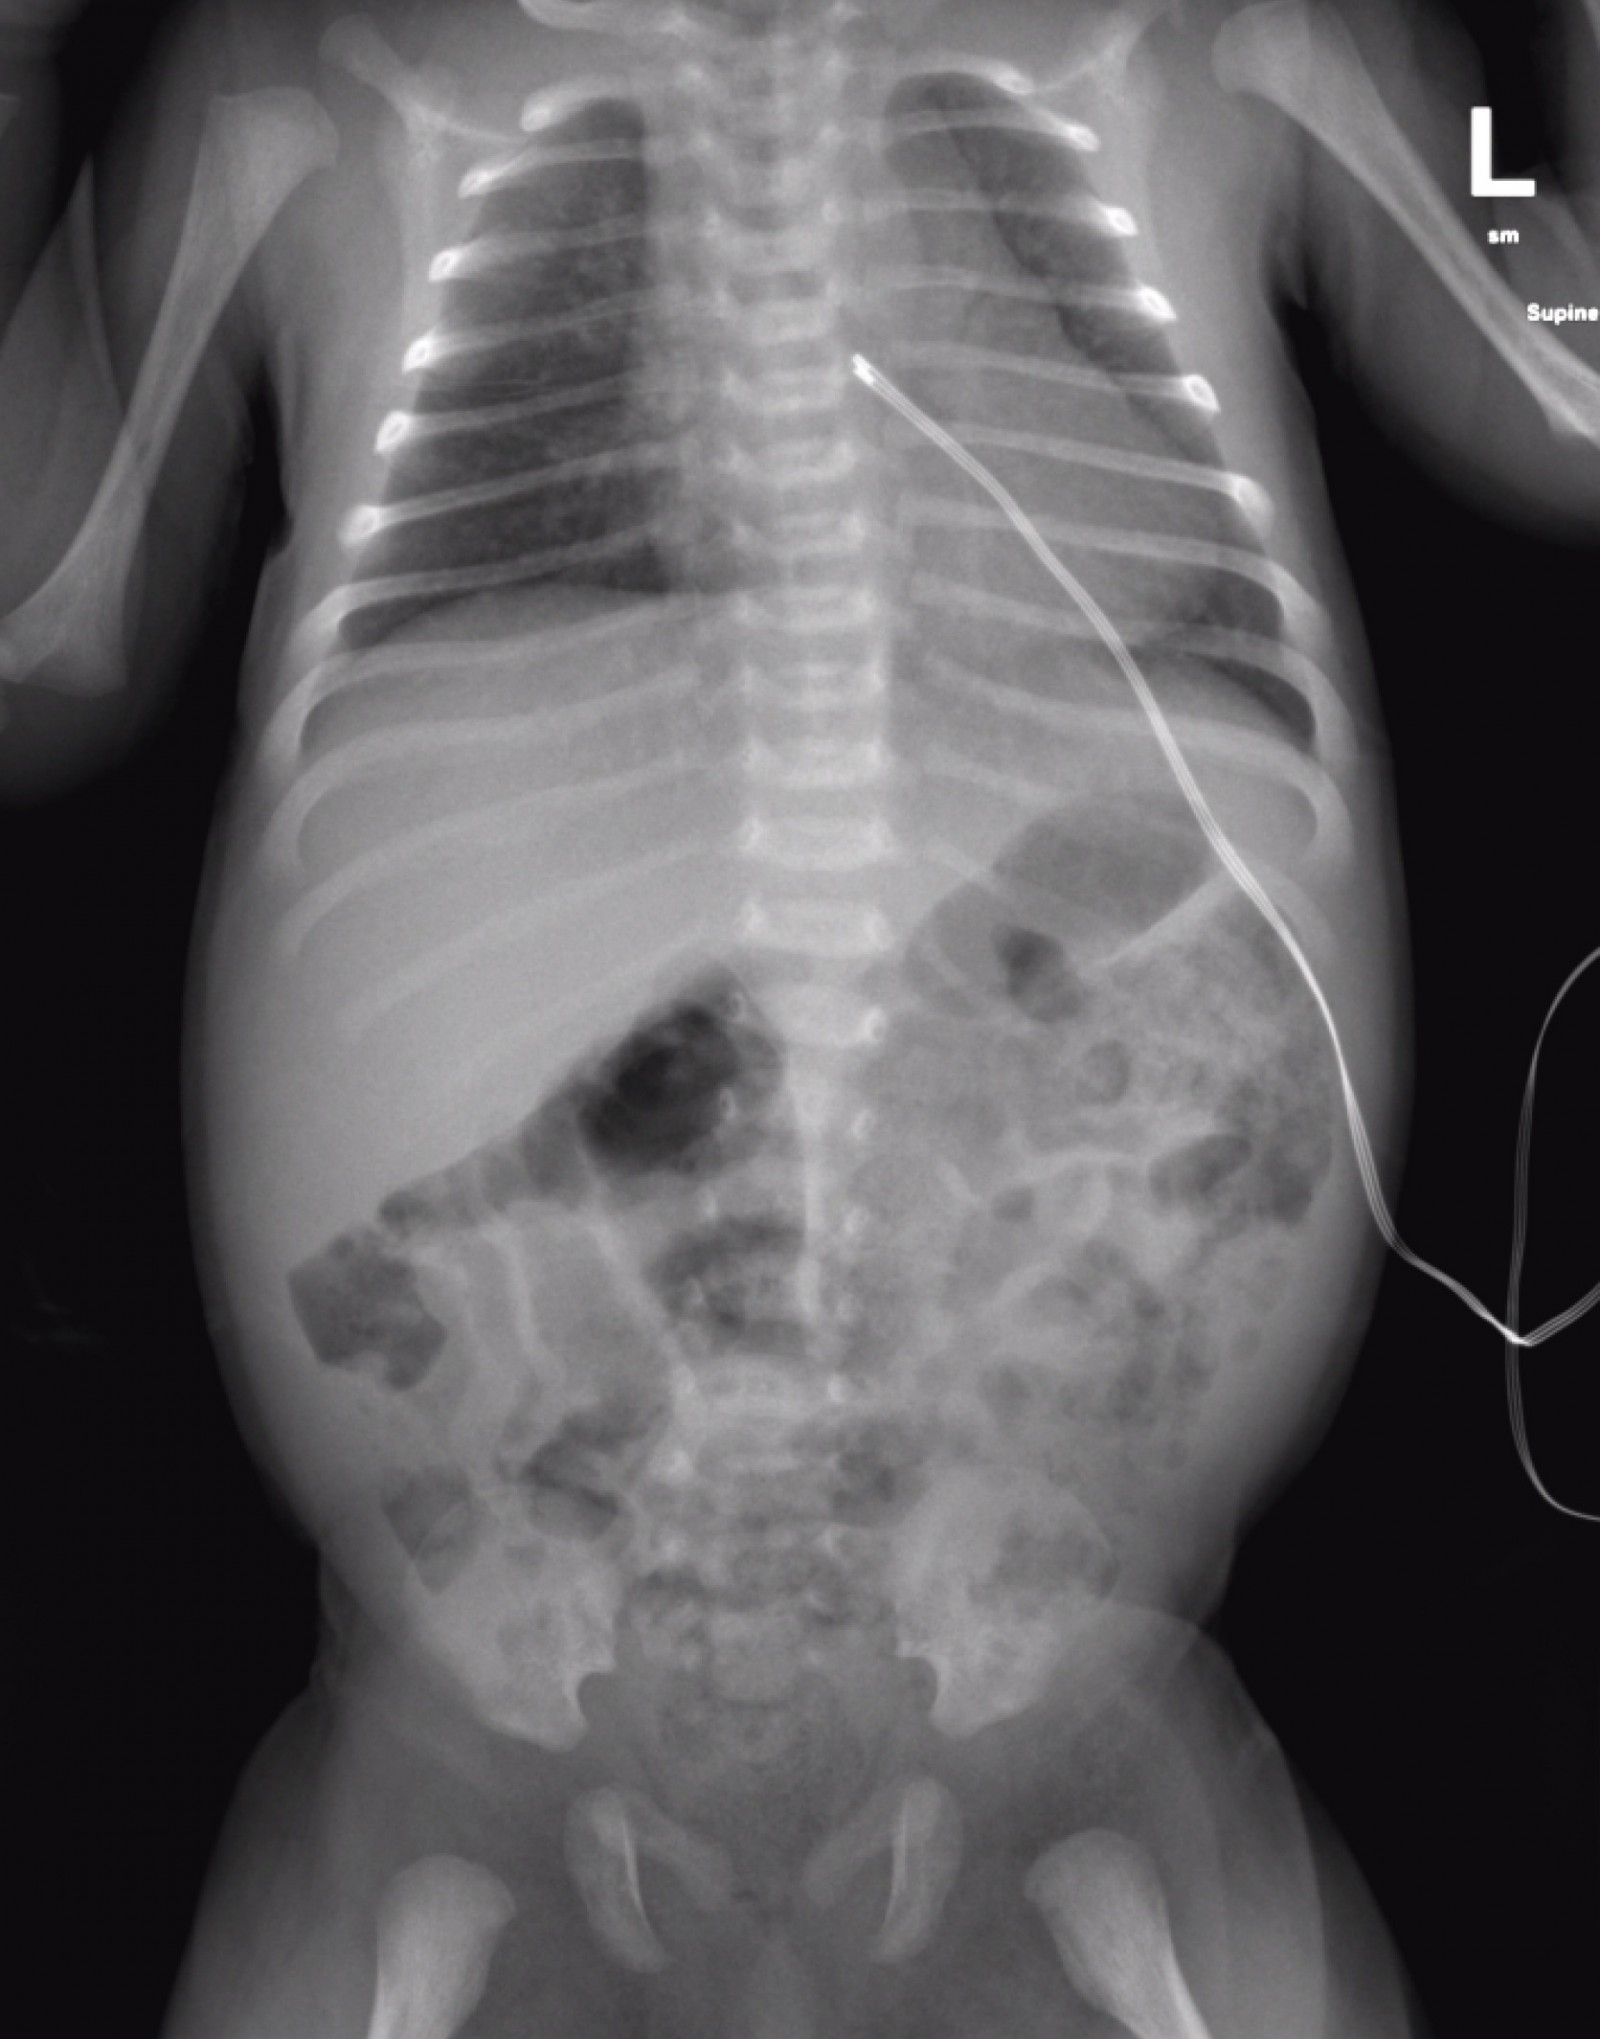

Due to concerns about an acute abdomen, the local and paediatric surgical teams were consulted, and the case discussed with the paediatric intensive care unit team for potential transfer given the clinical condition. Ultrasound abdomen and upper gastrointestinal barium swallow were normal with no evidence of intestinal malrotation. Abdominal X-ray revealed no signs of necrotising enterocolitis (Fig1). As investigations for gastrointestinal pathology were unremarkable, the possibility of parechovirus was considered. Parechovirus PCR of cerebrospinal fluid was found to be positive.

Figure 1: Abdominal plain radiography taken on admission. Mild faecal loading with no pneumatosis intestinalis or free intra-abdominal air.